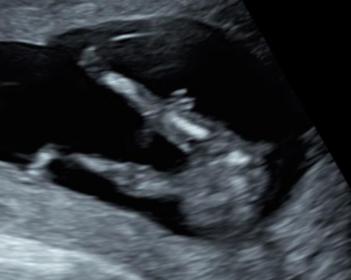

Self-made ultrasound at 16 weeks!

Hi, I am a pediatrician and did try to do an ultrasound on myself (with some watching colleagues) at 15+4 weeks for a potty shot of our third baby.

As we normally use the ultrasound differently I am not experienced with fetusses! Now we have three opinions- I thought the thing between the legs was the cord- one colleague said it SO looked like a penis with scrotum in the one pic (she has a point), two others said "not enough evidence" to decide ;-)

What do you think? We have no nub shot from our (expert) scan at 12+4, only this potty shot. Attachment 41406